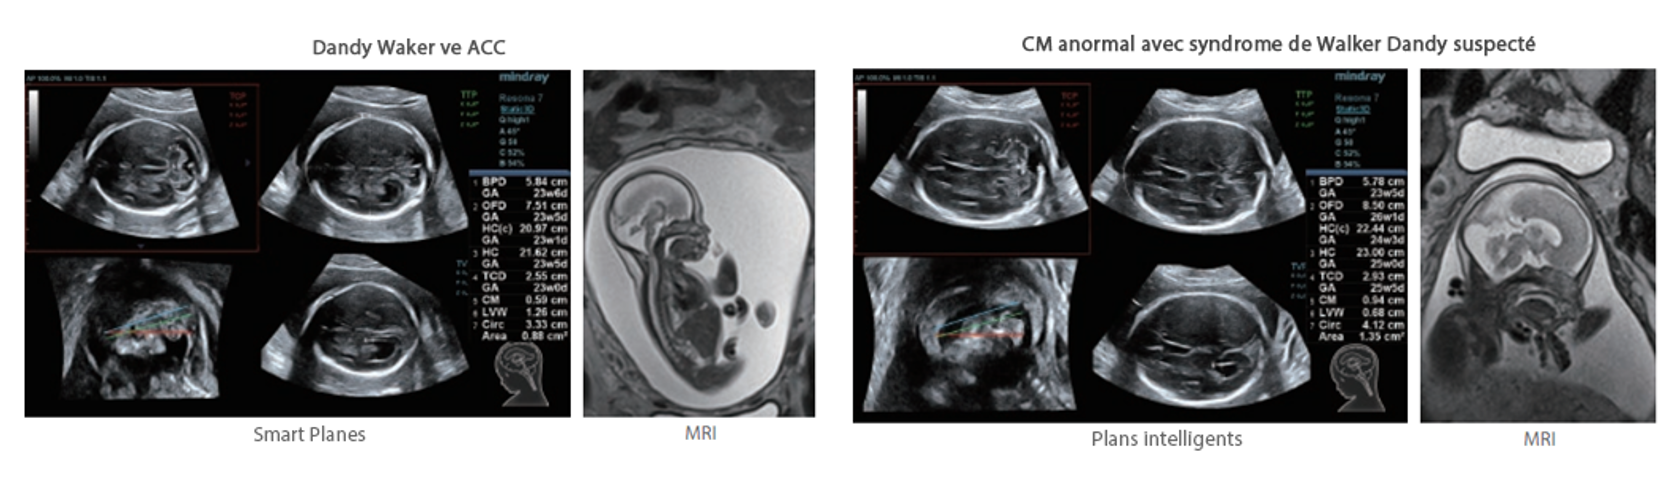

Resona 7, ĂŒstĂŒn dĂŒzeyde g?rĂŒntĂŒ kalitesine ek olarak, vaskĂŒler hemodinamik de?erlendirmesi i?in devrim niteli?indeki V Ak??? ile fetĂŒs CNS tan?lamas? i?in 3 boyutlu veri kĂŒmesinden dĂŒzlem g?rĂŒntĂŒsĂŒ alma konusunda en iyi birime sahip oldu?undan, klinik ara?t?rma yeterliklerini de art?rmaktad?r. En sezgisel, harekete dayal? ?oklu dokunmatik i?letim ile tĂŒm temel klinik ?zellikleri bir araya getiren Resona 7, ultrason yenili?i konusunda ger?ek anlamda yeni dalgalara ?ncĂŒlĂŒk ediyor.